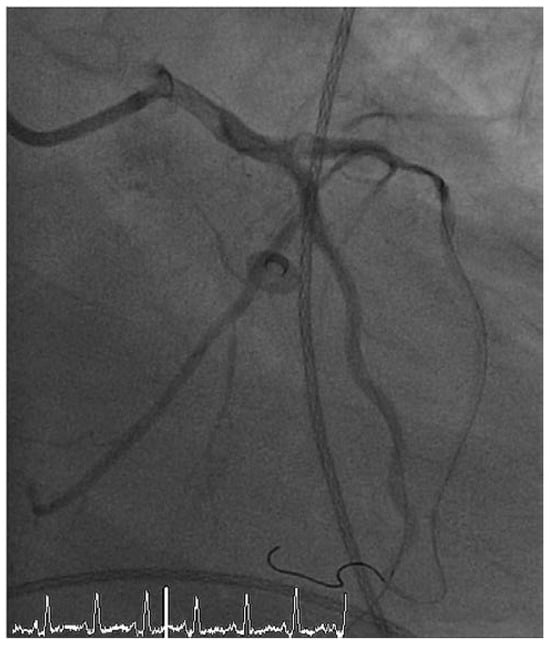

Case report A 22-year-old male experienced a presyncopal spell while studying for a university examination [...]